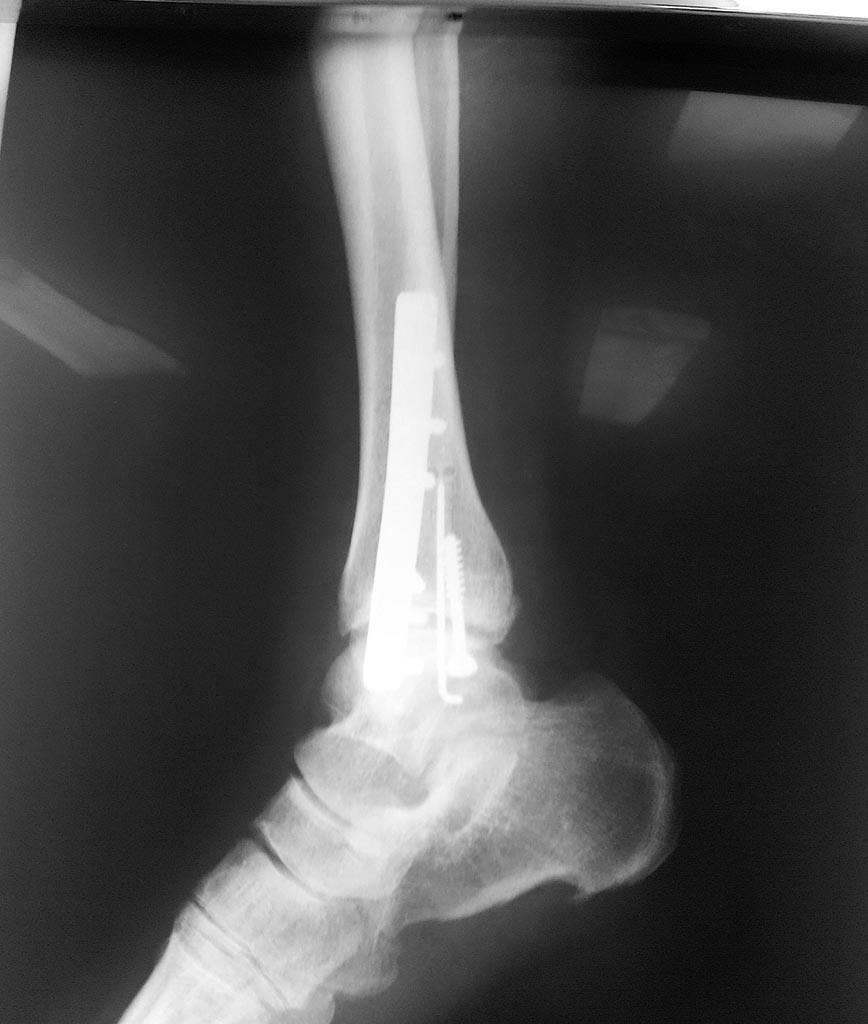

[Ortho] Лодыжки - подвывих стопы?

боковая